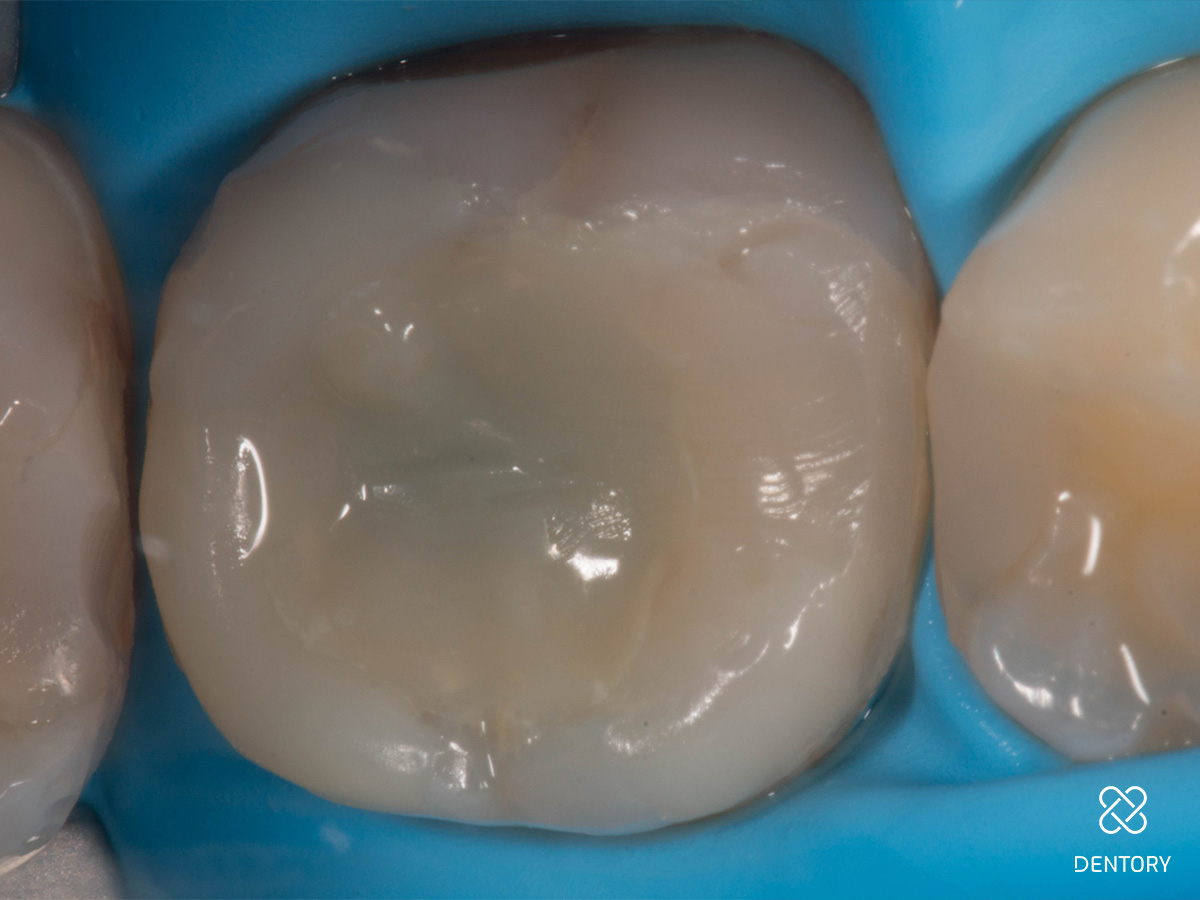

Abbildung 2

Entfernung der insuffizienten Füllung. Man kann erkennen, dass die Guttapercha aufgrund der hohen Transluzenz des damals verwendeten Materials durch die Füllung scheint.